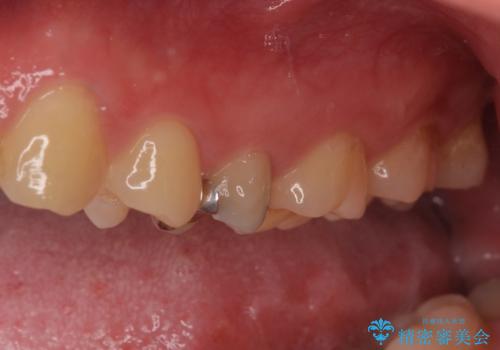

右上の被せものを除去したところ、中で歯が割れていたため、部分矯正で引っ張り出すことになりました。

歯を引っ張り出したり、歯肉の手術の経過待ちの間に、患者様のご希望で他の歯の虫歯治療も行いました。

・基本的には失活歯(根管治療済の歯)が対象となります。

・約3か月ほど引っ張り出します。

・両どなりの歯に一時的にワイヤーを接着します。

・十分に引っ張り出した後、歯肉の手術が必要となります。

・歯肉が落ち着いてから最終的な被せものの製作となります(約3か月)。

・歯の割れ方によっては引っ張り出す対象外となります(抜歯になります)。